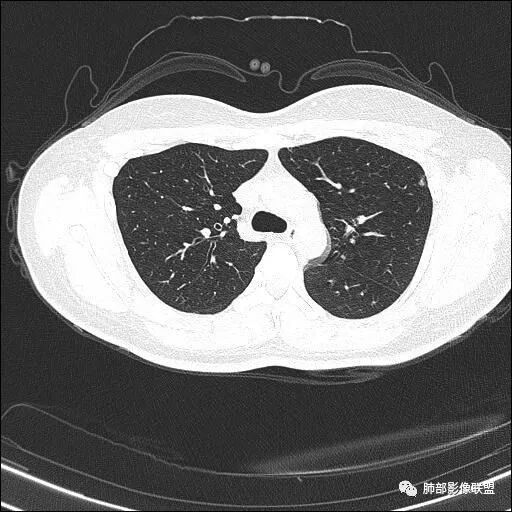

【每日晨读】双肺上叶多发薄壁空洞

双肺上叶多发结节影及纤维索条影,部分结节内部可见空洞形成,形态欠规则,洞壁厚薄均匀,以胸膜下分布为主,多灶性,多态性,临床年轻女性,体检发现,考虑结核,寄生虫?NTM.

双肺上叶尖段分布为主多发囊腔伴斑点,斑片影,囊腔壁不规则,部分内见分隔。考虑结核可能

两肺多发囊或空洞(部分腔内不干净可见间隔影)+多发结节 (右侧胸膜下的结节显著)+左肺尖斑片影。年轻女性,体检发现。考虑结核?鉴别PLCH(奇异囊加结节,吸烟男性多见),转移瘤(要有原发肿瘤病史)

双肺上叶多发结节影,形态不规则,部分结节内部可见空洞形成,洞壁薄,胸膜下分布为主,年轻女性,体检发现,考虑结核

2.双肺多发薄壁空洞影、条索影及结节影,边界较清楚,密度偏高不柔和,散乱,但有成簇倾向或堆积感,胸膜下分布为主,双肺上叶分布为主。

3.空洞相当不规则,缺乏张力,未见血管穿行,未见壁结节,未见液平。

4.双肺门及纵隔未见肿大淋巴结。未见胸腔积液。